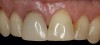

(26.) Facial and occlusal views of the soft-tissue contour achieved after 3 months of provisionalization. The tissue is thick with a harmonious gingival contour and zenith position.

Figure 26

(27.) Facial and occlusal views of the soft-tissue contour achieved after 3 months of provisionalization. The tissue is thick with a harmonious gingival contour and zenith position.

Figure 27

(28.) Facial view and radiograph of the final implant-supported crown.

Figure 28

(29.) Facial view and radiograph of the final implant-supported crown.

Figure 29